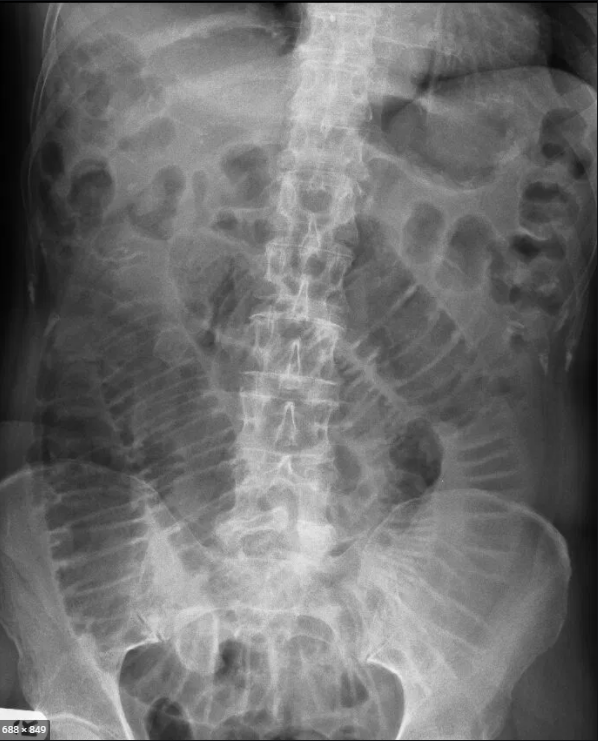

16

Q

Qual o sinal? obsstrução de?

A

Pregas não circunferenciais incompletas

Obstrução de intestino grosso